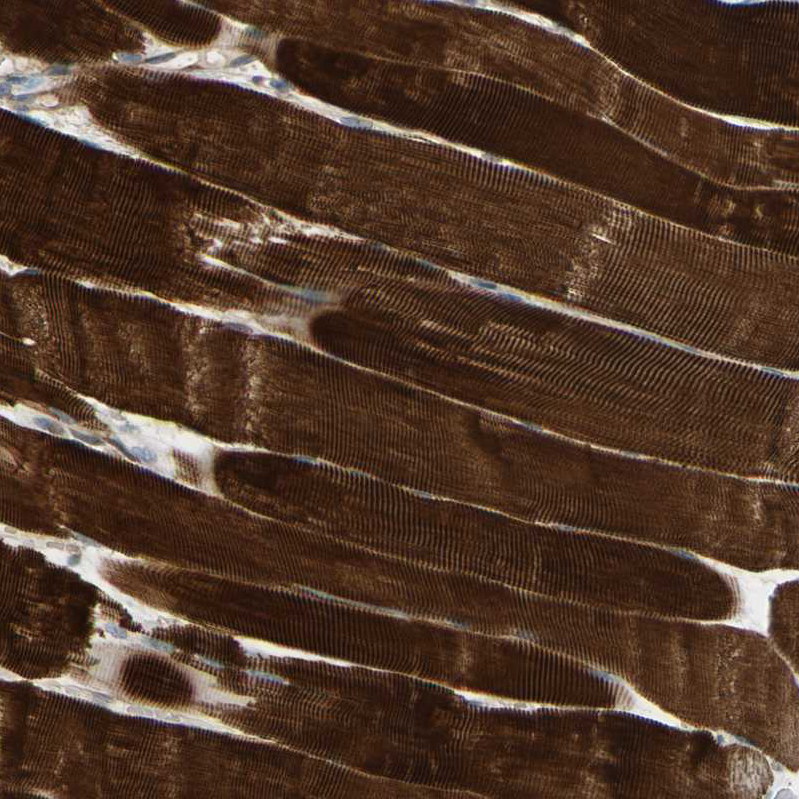

Immunohistochemical staining of human rectum shows strong cytoplasmic positivity in glandular cells.